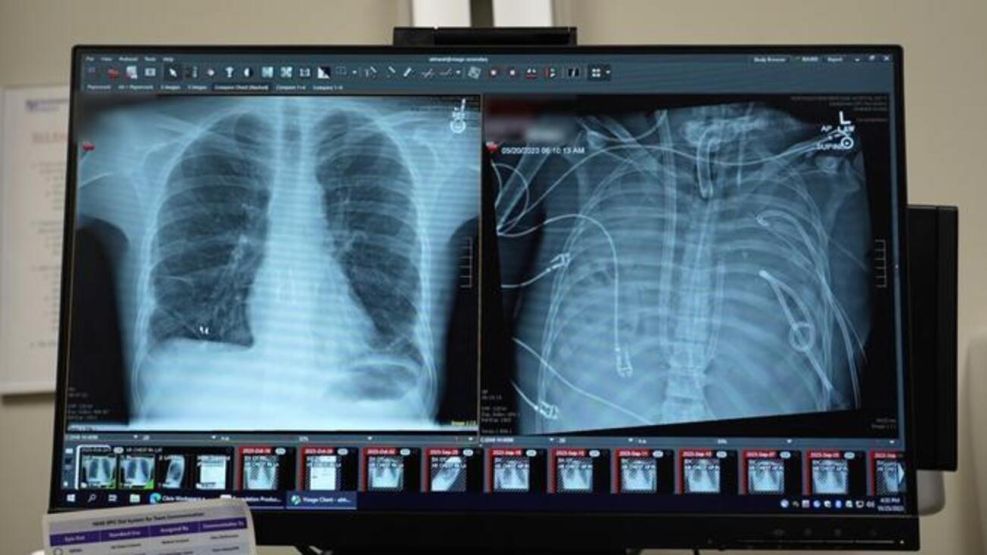

Un paciente de 33 años sobrevivió dos días sin pulmones mientras esperaba un trasplante doble en un hospital de Estados Unidos. El procedimiento, publicado en la revista Med, marcó un hito en la cirugía torácica y en el tratamiento de cuadros respiratorios agudos irreversibles.

Sin pulmones | Captura de pantalla

Un equipo del Northwestern University Hospital, liderado por el cirujano torácico Ankit Bharat, extrajo ambos pulmones infectados de un joven con síndrome de dificultad respiratoria aguda (ARDS) para frenar una infección que avanzaba rápidamente y comprometía otros órganos. Durante 48 horas, el paciente permaneció con un sistema extracorpóreo que oxigenaba su sangre y reemplazaba de manera temporal la función pulmonar hasta que aparecieron órganos compatibles. El caso fue cubierto por medios especializados y portales de ciencias como Robotitus.